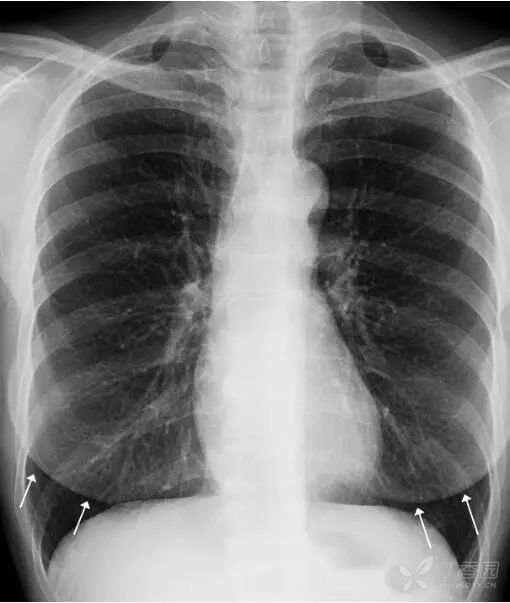

女性乳腺 女性乳腺相对胸部其他软策划较厚,因此在胸部正位X线平片上可以显示,通常重叠在两肺下野导致其密度增高,易被误认为肺内实变或肺内炎症。

上图女性乳腺影重叠在两肺下野,导致两肺下野对称性密度增高,乳腺形成投影的下缘(白色箭头)是清晰锐利的并且呈半圆形,常向外与腋部皮肤连续。没有乳腺重叠的两肺肋膈角区域更透亮。

鉴别:①两侧乳腺常规比较对称,所以在正位胸片上,乳腺重叠导致的两肺下野的密度增高也是比较对称的。而两肺下野均有病变且有分布比较对称的病理情况是比较少见的。②乳腺影的下缘清晰锐利且呈半圆形,向外与腋部皮肤连续。而肺内的病变不会延续到两肺以外。